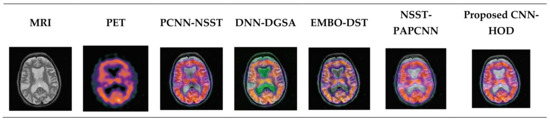

The fused images for the three dataset images are shown in Figure 5, Figure 6 and Figure 7. In this part, the proposed approach is compared with the existing approaches such as NSST-PAPCNN [20], EMBO-DST [12], DNN-DGSA [14], and PCNN-NSST [15] by regarding the parameters such as edge information retention (QAB/F), average gradient (AG), standard deviation (SD), mutual information (MI), entropy (EN), spatial frequency (SF), and fusion factor (FF). Figure 4 describes the fusion results of CT and MRI. Figure 5 describes the fusion results of CT and PET images. Figure 6 and Figure 7 describe the fusion results of the CT and PET images as well as the CT and SPECT images. From the comparative analysis, the results reveal that the proposed approach attains better performances than with other approaches. Table 3, Table 4 and Table 5 describe the objective computation of various methods on medical image fusion for CT and MRI, CT and PET images, and CT and SPECT images. The results (Table 6) show that the proposed approach has better results when compared with other approaches.

Figure 5. Fusion results of CT and MRI.

Figure 6. Fusion results of CT and PET images.

Figure 7. Fusion results of CT and SPECT images.